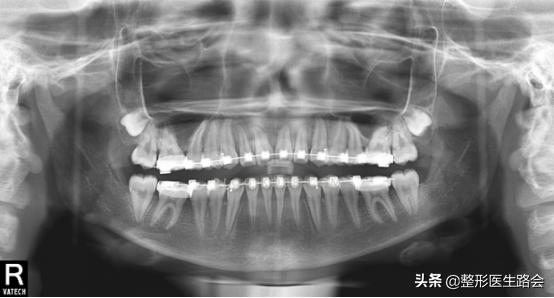

从反颌的形成来看,总体可分为两类。

一种是单纯性的由于牙齿排列错乱而造成的,上下颌的发育都是正常的,位置也是正常的。

而另一种是骨性反颌,表现为上颌骨发育不足,即后缩;下颌骨发育过度,即前突。造成面中部凹陷,侧貌为新月形,影响美观和功能。

这是造成“猪腰子脸”的根本原因——骨性凹陷。

上颌骨发育不全会造成眼下到上唇之间,也就是整个中面部出现一个高低落差感,皮肉会在这里出现断层。

如果是第一种呢?只需要牙科医生重新排列牙齿就可以了。

而如果是另一种是骨性反颌,就需要通过反颌手术才能彻底矫正成功!